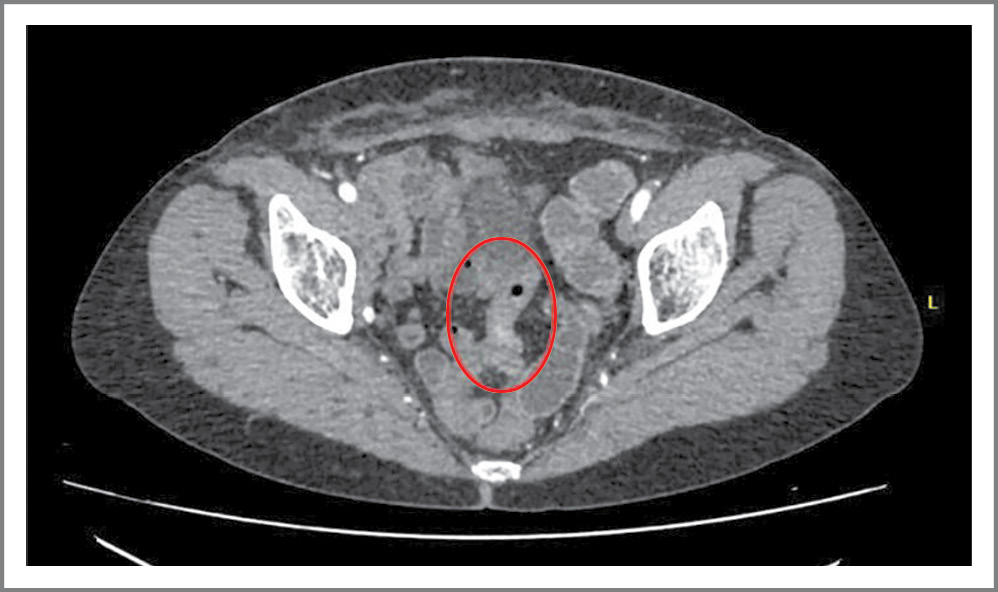

С целью исключения рецидива РТМ пациентке выполнены КТ органов грудной, брюшной полостей и МТ с контрастированием, колоноилеоскопия. В прямой кишке выявлены единичные телеангиоэктазии – проявления постлучевого проктита. По данным КТ во всех отделах визуализирована ТК. Рельеф ее СО сохранен. В МТ в средних петлях ТК визуализирован сегмент с суженным просветом до 1–2 мм, протяженностью до 40 мм, с циркулярно утолщенными до 5 мм стенками (рис. 1).

Рис. 1. КТ брюшной полости. Постлучевая стриктура тощей кишки.

Fig. 1. Abdominal CT scan. Post-radiation stricture of the jejunum.

Отмечено некоторое повышение накопления контрастного препарата стенками кишки на этом уровне. Проксимальнее описанной зоны определено инородное тело плотностью 14000 HU – видеокапсула (рис. 2).

Рис. 2. КТ брюшной полости. Видеокапсула в просвете тощей кишки.

Fig. 2. Abdominal CT scan. Video capsule in the lumen of the jejunum.